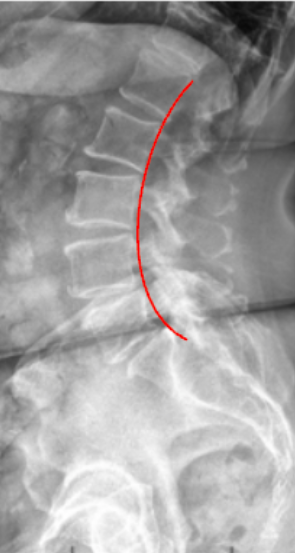

George’s Line—also known as the Posterior Vertebral Body Line—is a sagittal alignment assessment used to evaluate vertebral body translation and spinal stability.

It is drawn along the posterior margins of each lumbar vertebral body on a lateral X-ray and should form a continuous, smooth curve from L1 through the sacrum.

Any disruption or step-off between adjacent vertebrae suggests anterior or posterior displacement—commonly associated with spondylolisthesis, fracture, or ligamentous injury.

• Using a straight edge or digital PACS line tool, draw a smooth curve following the posterior vertebral borders.

• A smooth curve indicates normal alignment.

• A step-off or break indicates vertebral translation.

• If discontinuity is noted, quantify displacement by measuring the horizontal distance (in mm) between posterior body margins of adjacent vertebrae at the point of offset.